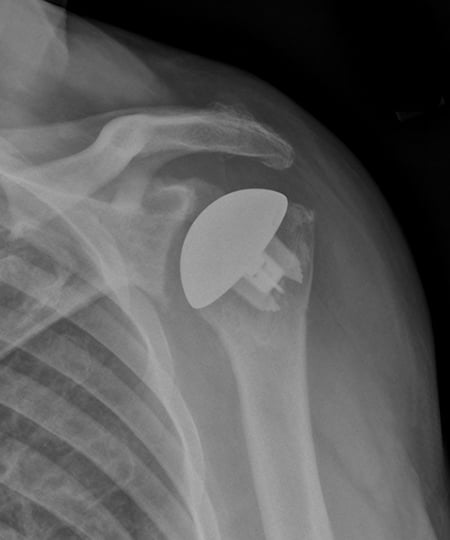

Figure 1: X-ray showing osteoarthritis of the shoulder joint, in which bones of the shoulder joint are in direct contact.

Figure 2: Anatomy of the shoulder, showing the implants after surgery.

Figure 3 (left): X-ray showing a traditional total shoulder replacement. Figure 4 (right): The Comprehensive Primary Shoulder System designed by HSS surgeons.